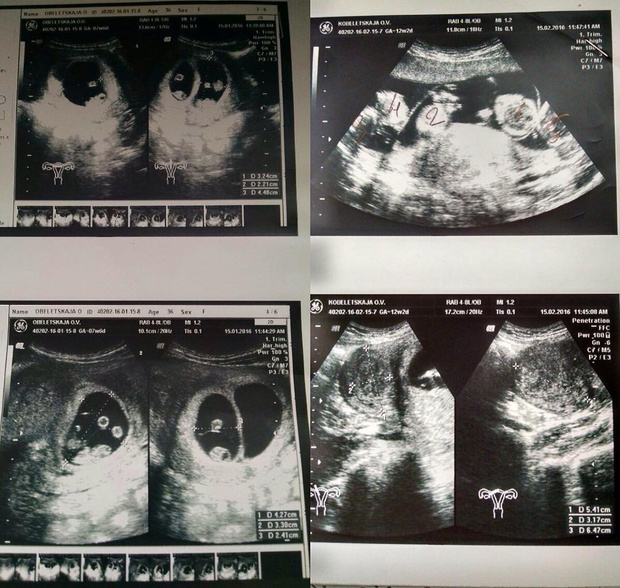

После новогодних праздников я отправилась на УЗИ.

Все было как у всех: голый живот, гель и датчик. Но когда доктор начала смотреть на экран, у нее сильно изменилось лицо.

Помню, как она начала вслух считать количество плодов и приговаривала, что за такое мне должны подарить дом у моря. Я не могла осознать происходящее и просто не поверила, что вынашиваю пятерых. Наверное, это просто ошибка! Однако на 12 неделе гинеколог снова подтвердил новость, и мы с мужем наконец поняли, что это реальность…